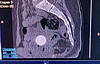

Первоначально специалисты подозревали наличие перелома или повреждения копчика (кокцигодиния). Для подтверждения диагноза пациентке назначили компьютерную томографию, по результатам которой был обнаружен инородный предмет.

– Кроме возможных повреждений в районе копчика, на снимках просматривался странный объект в полости малого таза. Дальнейшее обследование показало, что инородное тело расположено в верхней части влагалища. При осмотре на кресле выяснилось, что предметом является маленький каучуковый мячик. Его размеры и форма позволяли свободно проникнуть внутрь организма, однако самостоятельному выходу препятствовали особенности анатомии детского организма, – рассказала врач-гинеколог Кировской областной детской больницы Елена Колотилова, – Извлечение происходило крайне осторожно, без общего наркоза. Через небольшой промежуток времени шарик был извлечён, и здоровье девочки не пострадало.